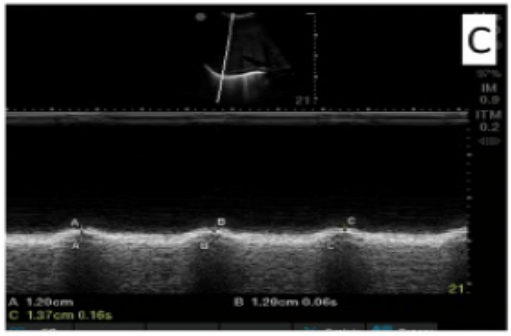

膈肌偏移(DUS)测量采用低频相控阵或曲线阵探头(2~5 MHz),探头位于锁骨中线的肋弓下方,患者处于半坐位,超声光束尽可能偏向颅骨并垂直于膈肌穹丘。膈肌被确定为一条覆盖肝脏和脾脏的明亮线。在吸气时,膜片应向探头移动。偏移量以M模式量化,M线垂直于运动方向。

我们可以在可合作患者最大吸气时测量偏移量(最佳偏移量),以评估膈功能障碍。

膈肌厚度(Tdi)的测量方法:高频线性探头(>7~10 MHz)垂直于侧胸壁,位于腋窝中线和腋窝前线之间,第9~10肋间隙之间。膈肌通常在距皮肤2~4 cm处可见,是一层低回声的内层肌肉,被腹膜和胸膜包围。以呼气末(Tdi,exp)和吸气末(Tdi,ci)为横膈膜胸膜与腹膜之间的距离,采用2D或M模式测量横膈膜厚度。